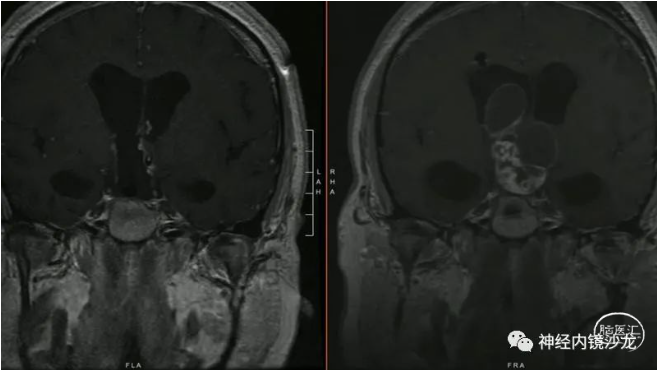

精彩图表

从事神经外科十余年,擅长神经外科肿瘤诊治,尤其是神经内镜微创手术治疗垂体瘤、颅咽管瘤、脑膜瘤等颅底肿瘤